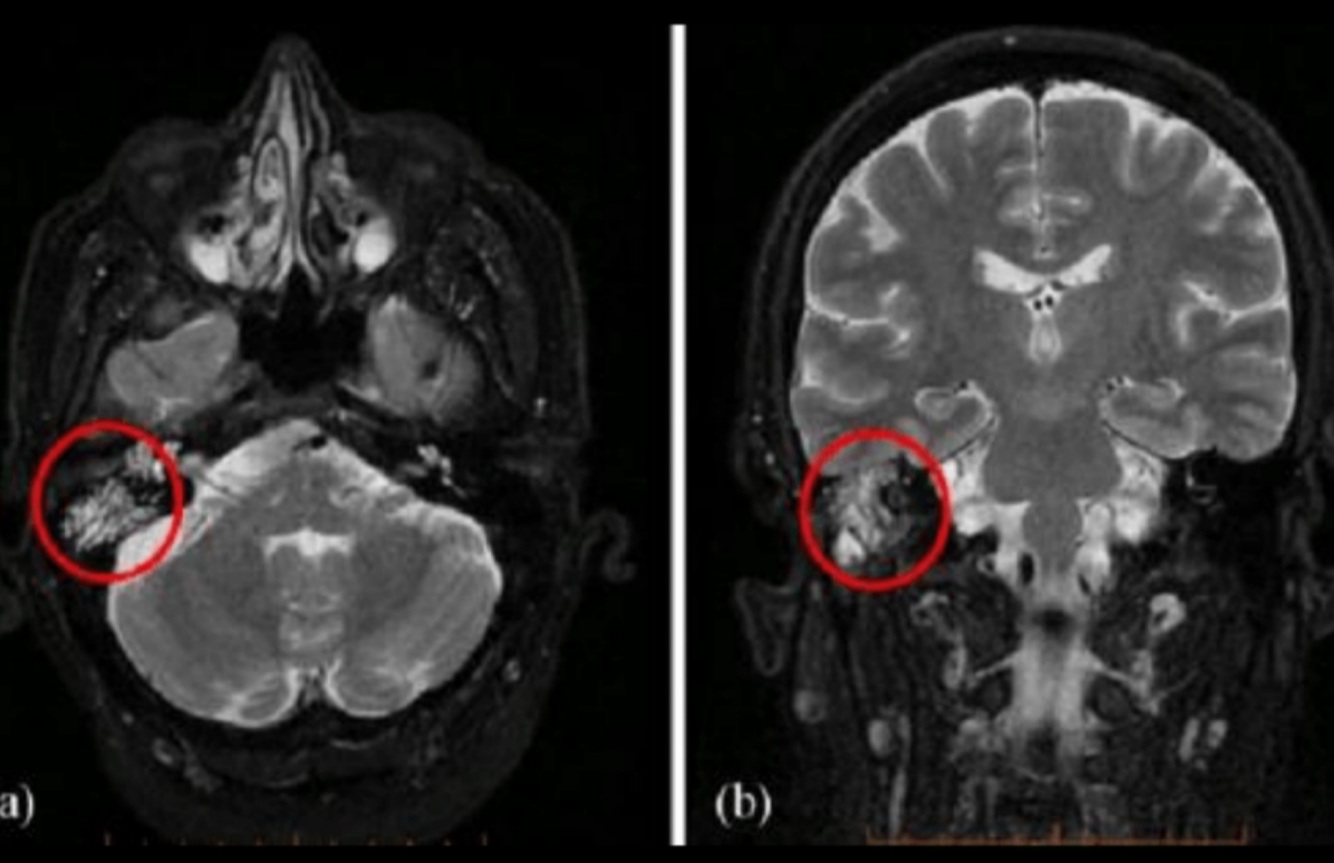

¿Para qué se usa la MRI?

Extensión intracraneal

➞Meningitis

➞Abscesos por complicación

Q

A

• Señal aumentada

• Disminución de señal en seno sigmoideo

• Capta contraste

Estudio de imagen dx para colesteatoma:

DWI

Hiperintensa en T2